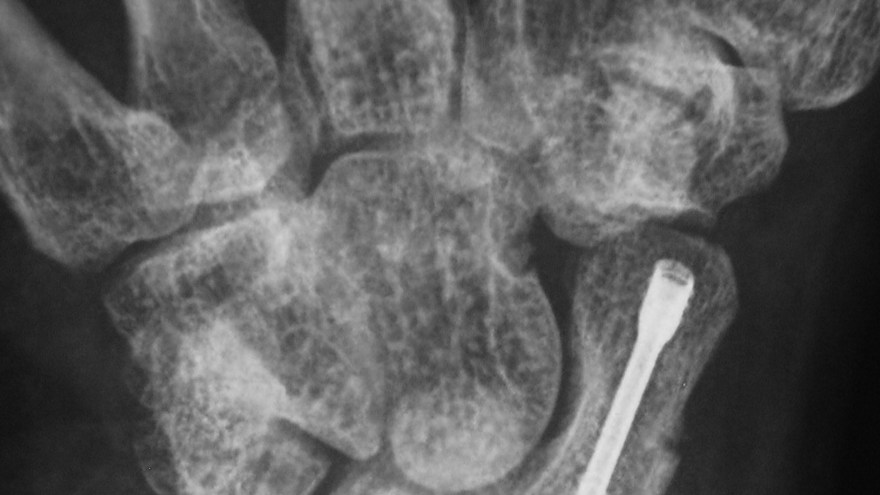

Bennetfraktur

Bennetfraktur är en intraartikulär luxationsfraktur genom basen av metacarpale I. Metacarpalbasen tenderar att luxera genom APL senans dragning i radiell-proxmal riktning. Frakturen behöver därför i princip alltid reponeras och immobiliseras internt med stift. Kan se väldig beskedlig ut på primära bilder men dislocerar succesivt genom senans dragning – klassificeras därför som ”lurig”.

Mekanism vid Bennetfraktur

Bennetfraktur där det ulnara fragmentet i basen på metkarpalen hålls kvar med hjälp av ligament i karpus. På grund av drag i abductor pollicis longus (APL) uppstår nästan alltid en diastas i frakturen. Diastasen i ledytan ger sekundärt artros. Dessa frakturer kräver således exakt fixation – vanligen i form av stift eller skruv.